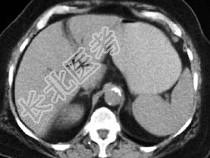

- 单项选择题男,30岁, 有胆结石病史,近日腹痛、腹胀, CT检查如图,应诊断为  (    )

- A、胆石症

- B、胆石性肠梗阻

- C、肠结核

- D、小肠克罗恩病

- E、小肠淋巴瘤